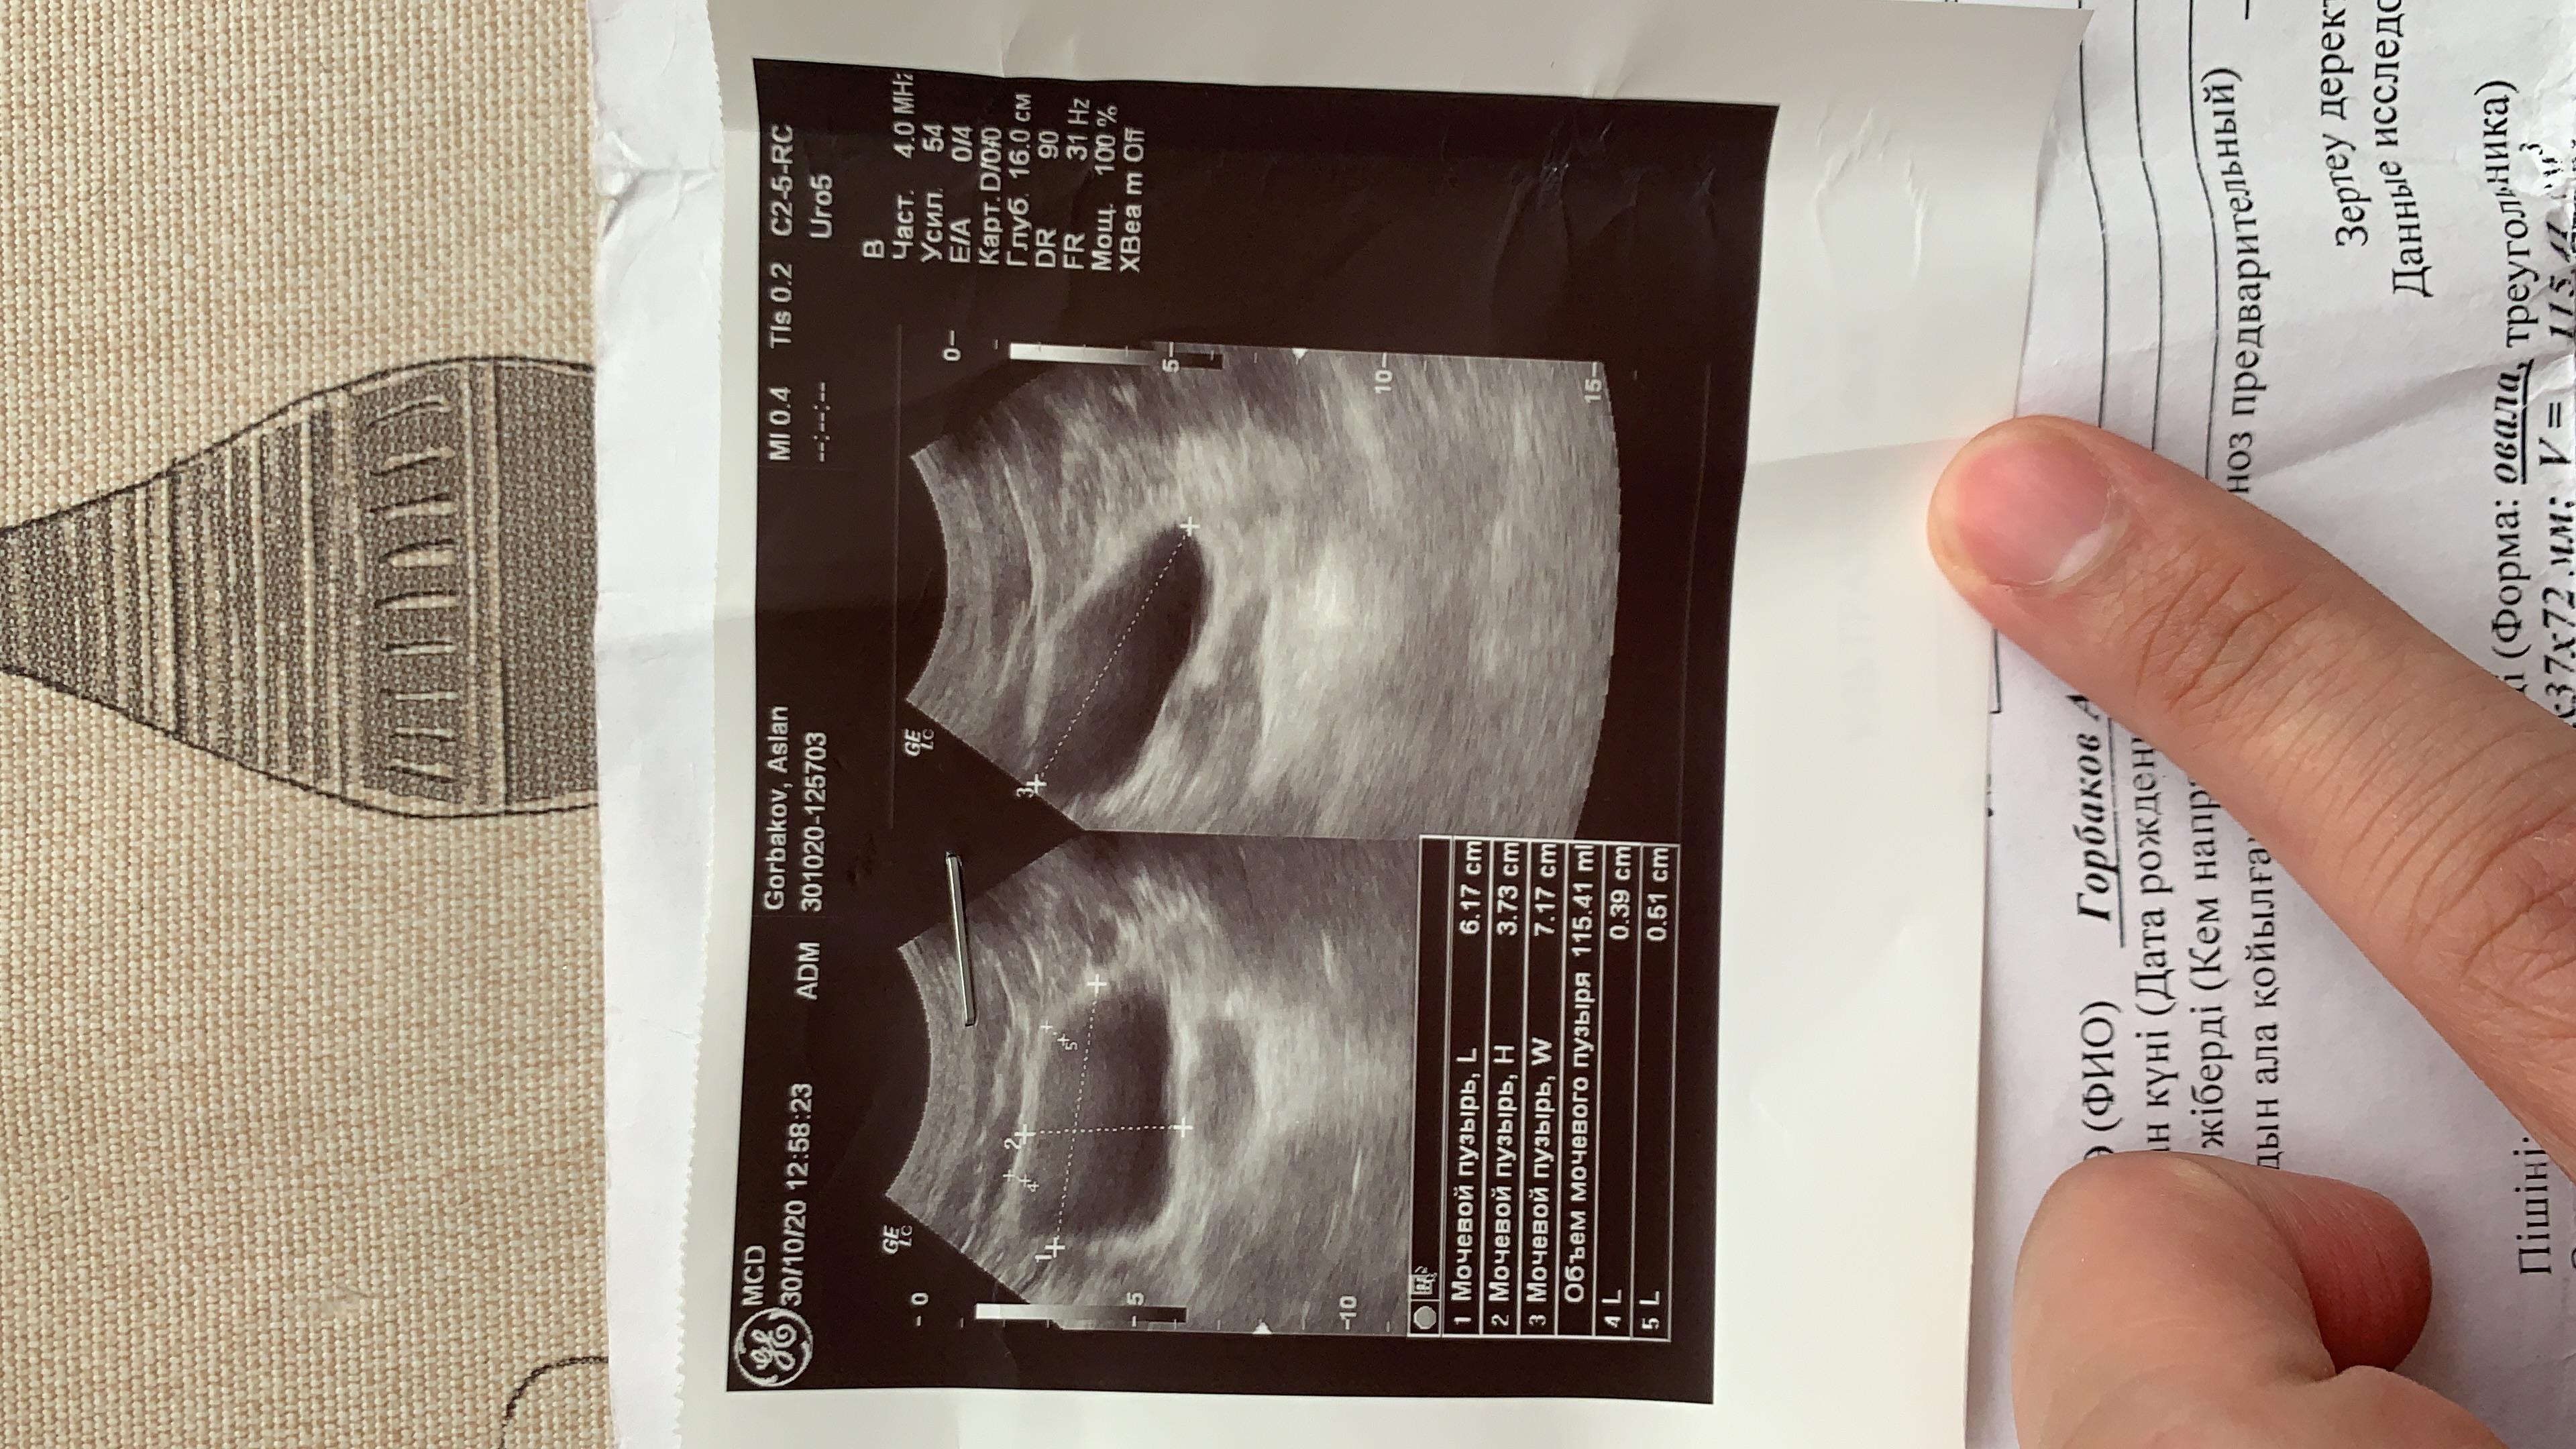

Застудил ноги, начал бегать в туалет, пошел в больницу, поставили диагноз хрон простатит и начали лечить, , лечили толку нет и после этого началась струя в разные стороны, сменил врача — то же самое, лечили простату. Мочевой не смотрели. Думали стриктура — сделали уретроцистоскопию, ее нет. Была чуть воспалена шейка. Сейчас обнаружили зппп, вылечили. Их нет. Симптомы остались, воспаления сняли. В узи выявили какую-то лунообразную впадину. Посмотрите пожалуйста, назначили лидазу/дистрептазу и амикацин. Анализы все чистые, флоры нигде нет.

Здравствуйте! По данным приведенных результатов обследования - имеет место хронический урогенитальный воспалительный процесс с проявлениями дисбиоза, с возможной более высокой концентрацией enterobacteriaceae/enterococcus в секрете простаты и эякуляте. Также - имеют место диффузные изменения предстательной железы с тенденцией к увеличению объёма простаты. Необходимо сделать бакпосев эякулята с определением чувствительности к антибактериальный препаратам( но не ранее, чем через месяц после последнего приёма любого антибактериального препарата по любому поводу). Для защиты предстательной железы, можно рекомендовать комплекс Гардапрост, который способствует остановке роста и деления клеток предстательной железы, уменьшению выраженности воспаления, уменьшению разрастания соединительной ткани в предстательной железе. Удачи!